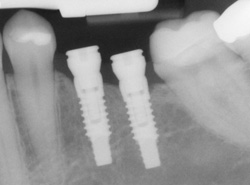

If you have missing teeth, it is crucial to replace them. Without all your teeth, chewing and eating can destabilize your bite and cause you discomfort. When teeth are missing, your mouth can shift and even cause your face to look older. Implants are a great way to replace your missing teeth.

implants processAn implant is a new tooth made of materials that looks just like your natural tooth. Your implant is composed of two parts that mimic a tooth's root and crown. The implant's "root" is a titanium rod placed into the jaw bone to act as a root. Once the rod is in place, a porcelain crown is attached to replace the top part of your tooth.

Implants may also be used to anchor dentures, especially lower dentures that tend to shift when you talk or chew. Plus, for patients with removable partial dentures, implants can replace missing teeth so that you have a more natural-looking smile.